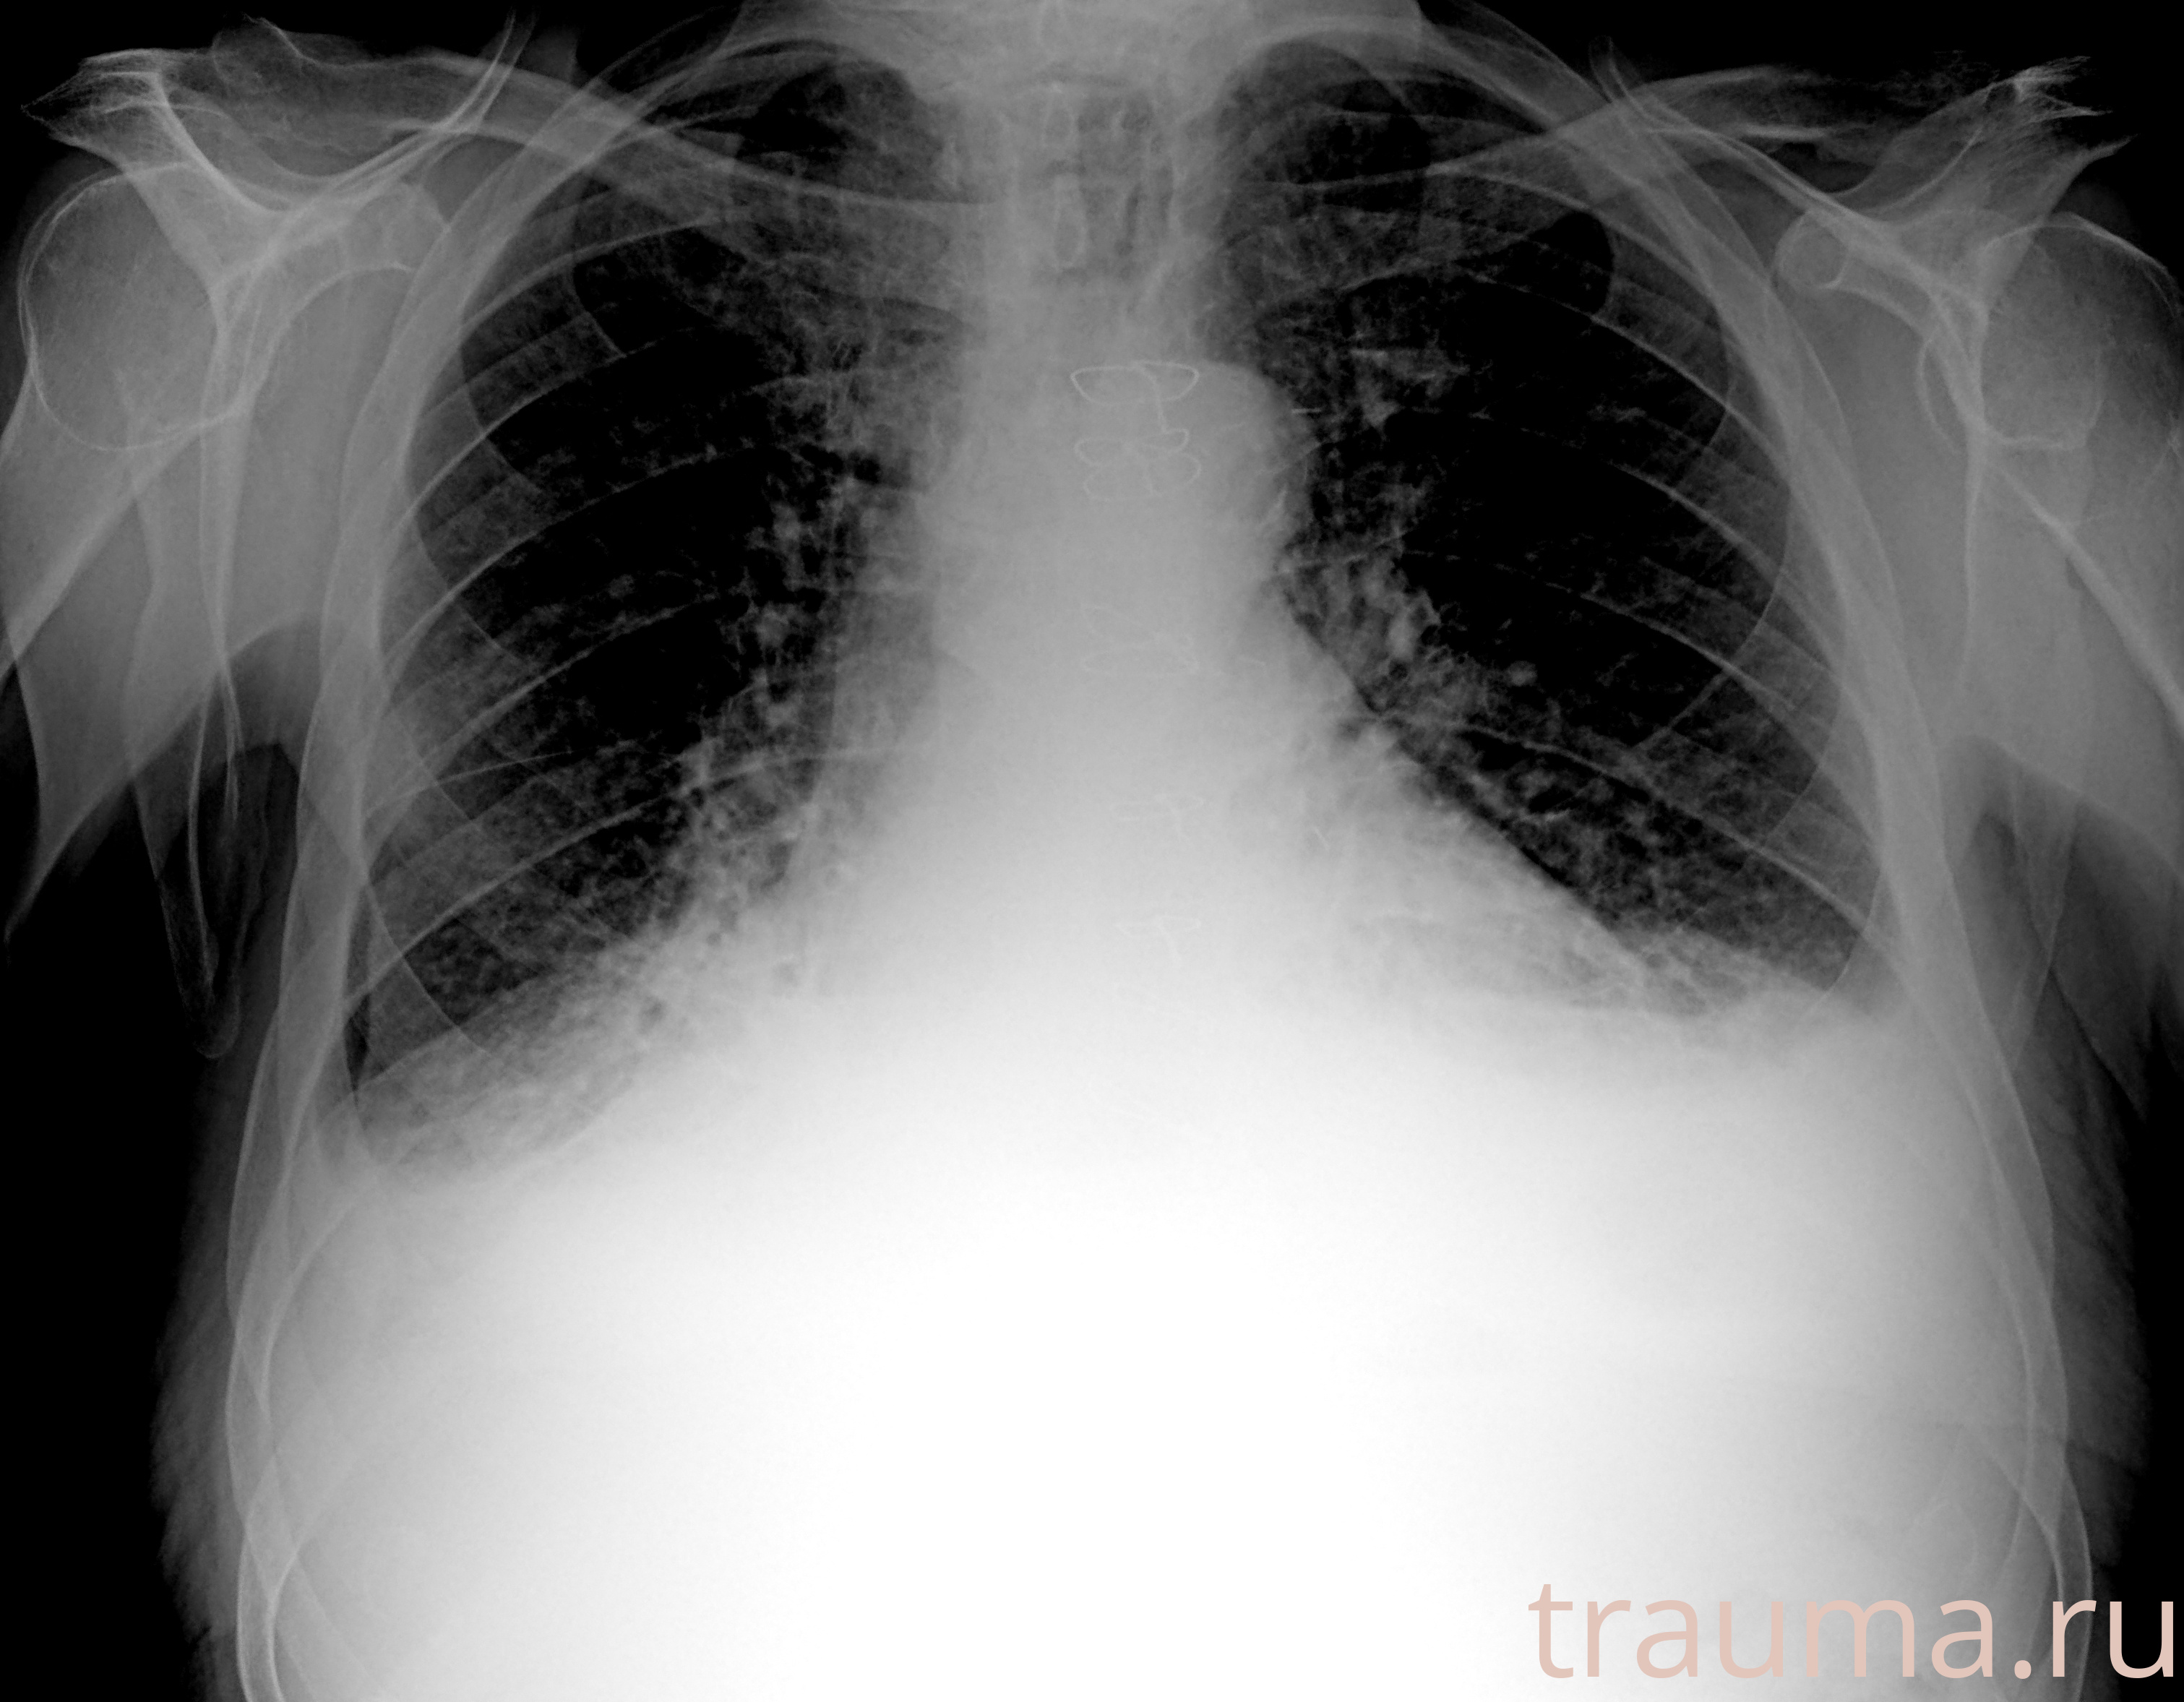

Рентген на дому: по вашему адресу приезжает врач-рентгенолог, травматолог-ортопед с мобильным рентгеновским аппаратом, проводит диагностику травмы или заболевания, делает необходимые рентгенограммы, дает рекомендации по дальнейшему лечению. Получить качественные снимки в домашних условиях возможно благодаря уникальной методике, разработанной МосРентген Центром для института  Склифосовского

при переломе шейки бедра и пневмонии от компании МосРентген Центр - партнера Института имени Склифосовского